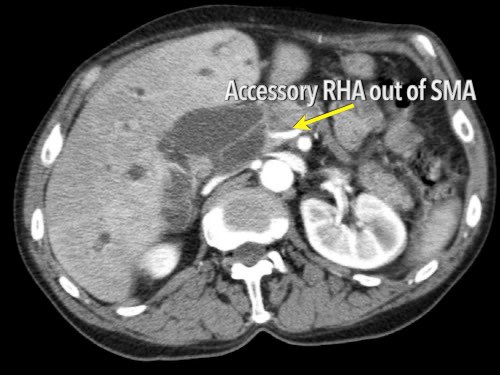

Các biến thể giải phẫu động mạch

Các biến thể giải phẫu

Giải phẫu động mạch gan được coi là bình thường chỉ gặp ở 55% dân số (hình minh họa).

Các biến thể giải phẫu động mạch gan được ghi nhận ở khoảng 40-45% dân số.

Các động mạch bất thường có thể đi qua vùng lân cận đầu tụy, làm tăng nguy cơ xâm lấn của khối u hoặc tổn thương do phẫu thuật.

Các động mạch gan có nguyên ủy bất thường có thể là dạng phụ thêm (accessory) hoặc dạng thay thế (replaced).

Động mạch gan phải phụ thêm là một động mạch gan phải bổ sung, trong khi động mạch gan phải thay thế có nguyên ủy bất thường và thay thế hoàn toàn cho động mạch gan phải chính thức (hình minh họa).

Ở những bệnh nhân dự kiến phẫu thuật tụy, điều quan trọng là cần đặc biệt chú ý tìm kiếm nguyên ủy bất thường của động mạch gan phải hoặc động mạch gan chung.

Các động mạch này xuất phát từ phía phải của động mạch mạc treo tràng trên (SMA) và đi qua vùng lân cận đầu tụy, làm tăng nguy cơ xâm lấn của khối u hoặc tổn thương do phẫu thuật.

Tần suất được ghi nhận của các bất thường đặc hiệu này lần lượt là 11-21% và 0,5-5%.

Hình CT axial cho thấy một động mạch gan phải phụ thêm (mũi tên vàng) đi qua vùng lân cận một khối giảm tỷ trọng ở đầu tụy (đầu mũi tên).